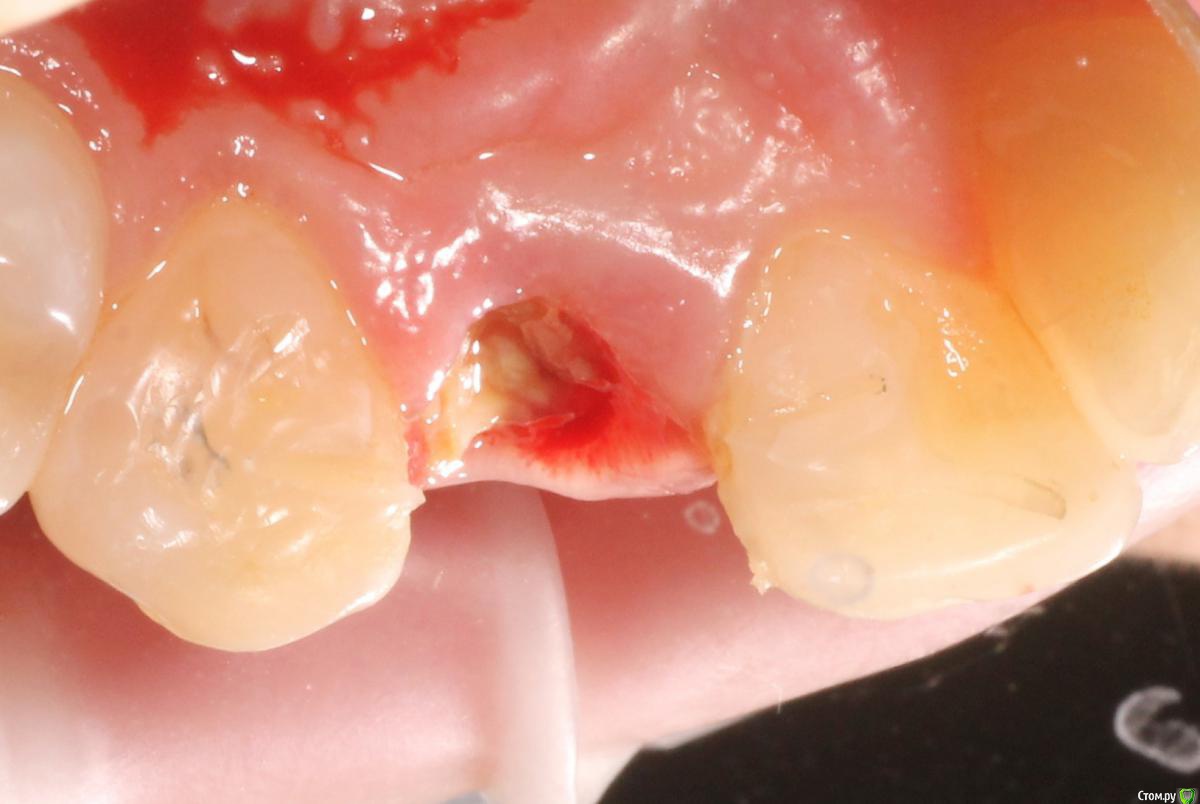

MenshikovDV Опубликовано 2 апреля, 2015 Поделиться Опубликовано 2 апреля, 2015 (изменено) Зуб 1.2 отлом коронковой части зуба, на период ожидания приема у хирурга и ортопеда (2 дня) приклеен к соседям. Вся процедура в одно посещение. Где-то часа два. Я ортопед, хирургия не моя, фото мои Изменено 2 апреля, 2015 пользователем MenshikovDV 19 Ссылка на комментарий

Brigita Опубликовано 5 апреля, 2015 Поделиться Опубликовано 5 апреля, 2015 на удаленном зубе какая то железячка хвостиком торчит))) Ссылка на комментарий

MenshikovDV Опубликовано 7 апреля, 2015 Автор Поделиться Опубликовано 7 апреля, 2015 ИНСТРУМЕНТ сломан в канале )) Ссылка на комментарий